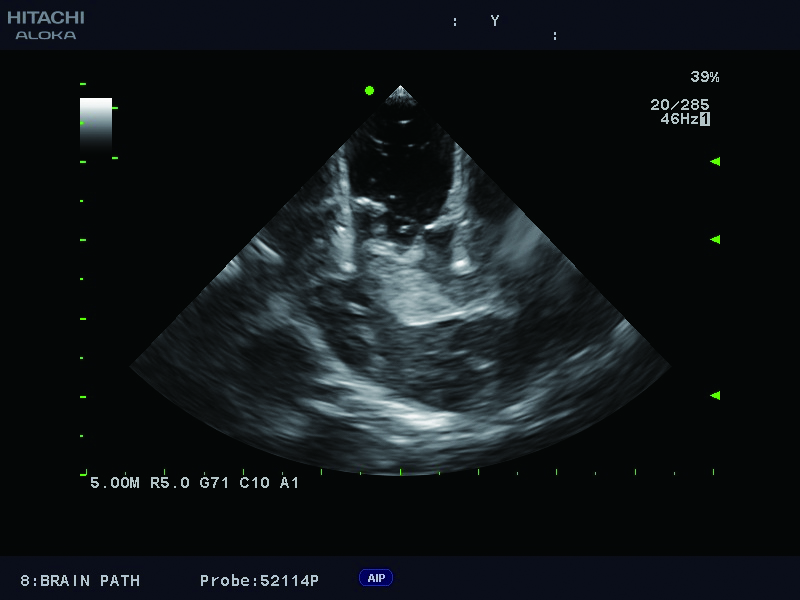

Superior guidance for all applications

Fujifilm Healthcare Americas is committed to designing tools that help surgeons navigate inside the human body and provide the necessary information to immediately make critical surgical decisions.

Fujifilm Healthcare's dedication to Surgeons provides outstanding ultrasound technology, professional support and the specialized tools necessary to best perform comprehensive real-time ultrasound imaging in Breast Surgery, General Surgery, Laparoscopic Surgery, Neurosurgery, Robotic Surgery and Surgical Oncology.

The Arietta 65 has many advanced and unique probes that fully cover the expanding range of procedures that benefit from ultrasound guidance.

The Arietta 65 has many advanced and unique probes that fully cover the expanding range of procedures that benefit from ultrasound guidance.